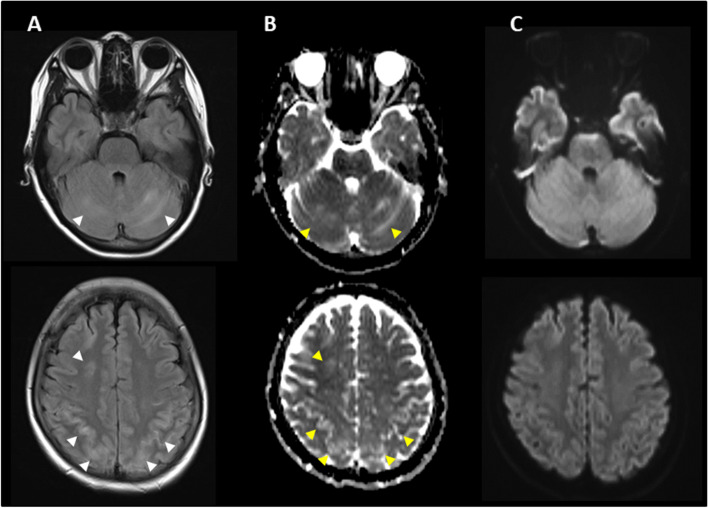

Five days after onset, brain MRI showed regions of hyperintensity in the right frontal lobe, bilateral parietal cortex and subcortex, and bilateral cerebellar lobes on FLAIR images (Fig. 1A). In addition, although the apparent diffusion coefficient (ADC) map showed elevations (Fig. 1B), no region of hyperintensity was observed on the diffusion-weighted image (DWI), suggesting angioedema (Fig. 1C). No abnormal findings were observed on brain magnetic resonance angiography (MRA) at the time of onset of the first headache (Fig. 2A). However, four days after the onset, multiple cerebrovascular spasms were observed, in which alternate contractions and dilations of several main arteries occurred (Fig. 2B). On the electrocardiogram (ECG) five days after the onset of the first headache, ST depression was observed in limb leads II, III, and aVF, and in the chest leads V3 to V6 (Fig. 3A). Ultrasound cardiography (UCG) showed a hypokinesis at the base of the side of intraventricular septum, with a slight decrease in ejection fraction (EF = 51.6%) and in fractional shortening (FS = 25.9%) (Fig. 4A). Although no symptoms of angina were observed 5 days after onset of first headache, left ventricular hypofunction leading to impending heart failure was suspected. Therefore, a calcium channel blocker and a nitrate were administered.

Fig. 1.

Brain magnetic resonance imaging (MRI) 5 days after onset of first headache. (A) Fluid-attenuated inversion-recovery (FLAIR) images showed hyperintense lesions in the right frontal lobe, bilateral parietal cortex and subcortex, and bilateral cerebellum (white arrow heads). (B) Apparent diffusion coefficient (ADC) map showed elevations in the same regions as the lesions observed (yellow arrow heads). (C) Diffusion-weighted image (DWI) showed no hyperintense regions